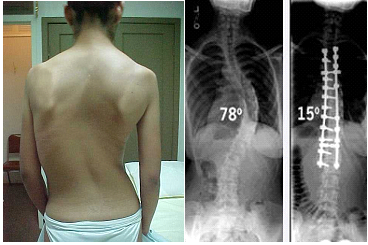

ESCOLIOSISLa escoliosis propiamente es la desviación lateral de la columna vertebral, asociada a rotación de los cuerpos vertebrales y alteración estructural de ellos. El término escoliosis proviene de una palabra griega que significa “torcido”. Se observa con frecuencia entre los 10 y 14 años y se inicia después de los 8 años, con un índice de 6 a 1 en las mujeres. Las personas pueden tener escoliosis a cualquier edad. El tipo más común es la escoliosis idiopática, o de origen desconocido, entre los niños de 10 a 12 años y al inicio de la adolescencia. Es a esta edad que los niños crecen con rapidez. Las niñas tienen una mayor predisposición a este tipo de escoliosis que los varones.

TRATAMIENTOEl tratamiento se inicia con la observación, ya que hay un importante número de casos que sólo hay que controlar y no requieren nunca tratamiento ortopédico. En general, a estos pacientes se les agrega ejercicios por medio de fisioterapia para mantener la columna flexible y mejorar la potencia muscular, abdominal y paravertebral. El siguiente grado en el tratamiento es el uso de corsé (el más empleado es el corsé de Milwaukee).

Está destinado a aquellos pacientes que están fuera del alcance ortopédico. Es decir pacientes con curvas sobre 45º, rígidas, mayores de 14 años, Risser 4, o que las curvas hayan aumentado dentro del corsé. El índice de Risser para estimación de maduración ósea, evalúa el grado de aparición del núcleo de osificación de la cresta ilíaca y su fusión al ala ilíaca, como se observa en la tabla. El grado de madurez ósea es otro de los factores pronósticos de la escoliosis idiopática, existiendo una mayor progresión de la curva en niños con un grado de Risser 0 ó 1, que en grados 2 a 5. La ventaja de utilizar este método es que las alas ilíacas están frecuentemente incluidas en la radiografía, por lo que sería innecesario contar con radiografías adicionales para la estimación de edad ósea(4). Indice de Risser

También requieren tratamiento quirúrgico para su corrección, aquellos pacientes que alcanzaron su maduración ósea y presentan curvas sobre 45º. El objetivo del tratamiento quirúrgico es estabilizar la columna ya que, de lo contrario, las curvas seguirían progresando y haciéndose cada vez más rígidas. El tratamiento quirúrgico pretende básicamente disminuir la magnitud de las curvas y mejorar las deformaciones estéticas. Esto se logra a través de la fusión de la zona de columna comprometida, luego de la corrección de las curvas con instrumental de distracción, compresión y desrotación de los cuerpos vertebrales, con sistemas de barras y ganchos o sistemas de Luque.